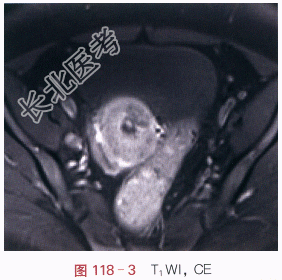

影像学资料如图118-1~图118-4所示。

读片分析:宫颈见内生型肿块,自宫颈外口向颈管内生长,侵犯宫颈深部组织,宫旁组织未受累,T₁WI呈等信号,T₂WI稍高信号,信号较均匀;增强后,瘤体强化较明显、欠均匀,但低于邻近正常的子宫。